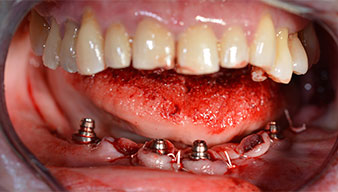

Направи се скенер с триизмерна компютърна томография (CBCT, Planmeca), за да се подпомогне планирането и да се намалят рисковете. Той показа, че качеството и количеството на наличната кост са достатъчни за операцията и имедиатното възстановяване, използвайки Fast & Fixed метод. Следвайки протокола за тази концепция, имплантите са поставени на 35, 32, 42 и 45 позиция. Ангулирането на дисталните импланти до 45° промени профила в задната зона и осигури по-голяма поддръжка в многоъгълната зона (Фиг. 3).

Fast & Fixed метод

Фиг. 3

Ангулираните абатмънти (35°) са завити в имплантите, за да компенсират отклонението от дисталните импланти, така че в резултат профилът на разположение на всички импланти да е възможно най-перпендикулярен на нивото на захапката. Това е предпоставка за оклузално поставяне на временна и впоследствие на постоянна протеза (Фиг. 15 и 16).

Импланти

Фиг. 15

Фиг. 16